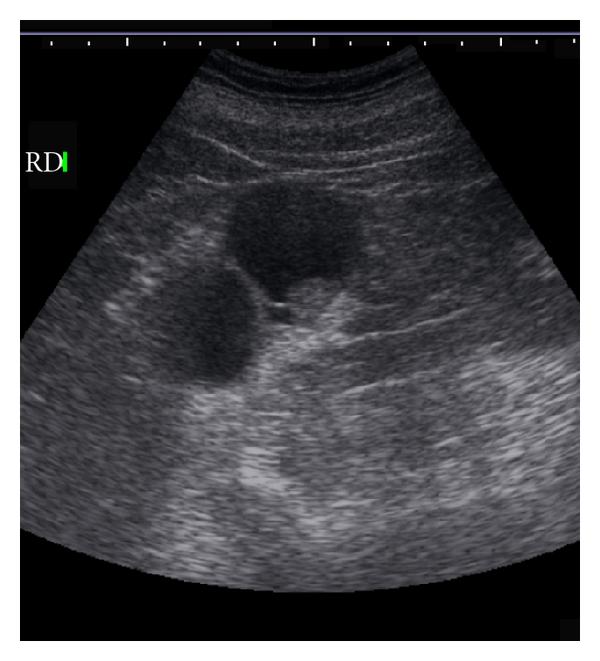

Ultrasound plays an important role in the detection and evaluation of these SRMs. While this technique may not be as sensitive as contrast-enhanced CT or MR for revealing SRM, US has been the initial technique in the discovery of a large number of these incidentally discovered tumors when the kidney is studied in the course of abdominal imaging. Sonography is very accurate in distinguishing liquid from solid tissue. Therefore, its major use in these small lesions is to help differentiate small cysts (see Figure 1) from small solid tumors [8]. Maintaining rigid criteria is necessary to maintain the high accuracy possible with this technique.

In the general population, renal cysts are the most common space-occupying lesions in the kidney. With this technique, 80% of detected renal masses are characterized as simple cysts [9] thus ending their diagnostic evaluation. The remaining 20% of renal masses require further study with CT or MR imaging [10]. Any mass detected that does not meet the strict sonographic criteria for a simple cyst should be further evaluated with CT or MR imaging of the kidneys. However, one or two thin septations may also be visible sonographically in simple renal cysts [11]. Because these findings are diagnostic, no further imaging or followup is needed in the evaluation of these lesions. However, other atypical features sonographically detected calcifications; more than two septations, septal thickening or nodularity, and the presence of solid components indicate that sonography alone will not be adequate for complete evaluation of these renal masses (see Figure 2). The addition of Doppler sonography, color Doppler sonography, power Doppler sonography [12, 13], and sonographic contrast agents may further improve the detection and characterization of renal masses. However, none of these techniques preclude the need for CT or MR imaging of renal masses that do not meet the sonographic criteria for diagnosis of a simple cyst.